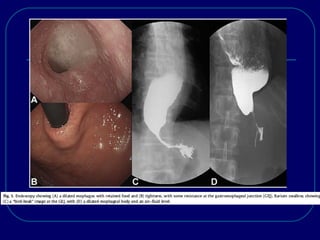

ACHALASIA:

 CXR show a widened mediastinum, air-fluid level& absent

gastric air bubble.

 Barium swallow shows a dilated esophagus, air-fluid level,

delayed esophageal emptying& a smooth, tapered “bird’s

beak” deformity at the LES.

Achalasia: barium swallow

ACHALASIA:  CXR showa widened mediastinum, air-fluid level& absent gastric air bubble.  Barium swallow shows a dilated esophagus, air-fluid level, delayed esophageal emptying& a smooth, tapered “bird’s beak” deformity at the LES.  Manometry show characteristic incomplete relaxation of the LES with swallows& complete aperistalsis in the body.  LES pressure may or may not be elevated.  Neither radiographic nor manometric criteria can effectively exclude achalasia secondary to cancer, so endoscopy must be performed prior to treatment.